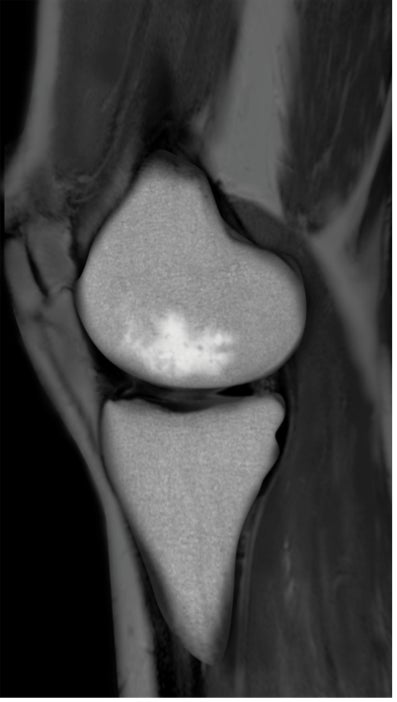

BML(Bone marrow lesion、骨髄異常陰影)はMRIで発見することのできる骨髄内の異常のことを言い、軟骨の下の骨の微小骨折による骨髄内の炎症または浮腫(水分が骨に溜まった状態)、壊死(骨が死んでしまった状態)をあらわすとされています。

BMLは痛みと強い関係があることが示されていて、標準的な保存治療のヒアルロン酸注射や近年注目されている再生医療のPRP療法でも改善しない関節痛の原因となっている可能性が指摘されています。

IOBPは体に金属を入れることなく、骨の痛みの改善や骨の再生が期待されている治療手技です。特に変形性膝関節症や特発性大腿骨頭壊死などの疾患に対しては、欧米を中心に治療の安全性や一定の有効性を示唆するデータが報告されています。その他の整形外科領域でも様々な疾患に対しての臨床使用の報告があります。しかしながら、本邦ではまだ実施例が乏しくその成績に対する見解は一定しておらず、まだ治療法としては確立されていません。以下に主な治療法を紹介します。